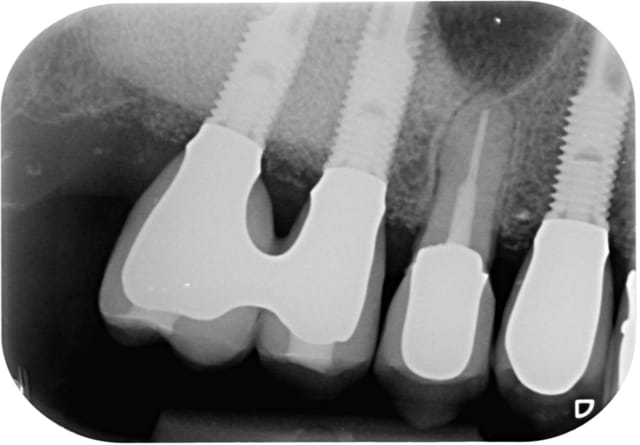

Bon alors revenons a cette 15.

On voit bien sur l'historique radio que la migration apicale a débuté entre janvier et mai 2014. Date à laquelle j'ai dû changer la 14.

A 10 mars 2008 hjqdhq - Eugenol

B 22 mai 2009 fhhmrm - Eugenol

C 04 juin 2009 vjcx5r - Eugenol

D 15 juin 2009 od7vwg - Eugenol

E 25 juin 2009 hht4ji - Eugenol

F 18 novembre 2009 hhywkg - Eugenol

G 21 janvier 2011 xurlrw - Eugenol

H 19 fevrier 2013 tvy4db - Eugenol

I  21 janvier 2014 gyys5o - Eugenol

J 21 mai 2014 i8zdgv - Eugenol

Jj 16 octobre 2014 clat7g - Eugenol

Jjj 16 otobre 2014 yevkyg - Eugenol

K  6 novembre 2014 lfkxbg - Eugenol

L  6 novembre 2014 gcsqeq - Eugenol

M  6 novembre 2014 gc5q3z - Eugenol

P  6 novembre 2014 cy54gy - Eugenol

Q  6 novembre 2014 vtispk - Eugenol

R  6 novembre 2014 nrhlqf - Eugenol